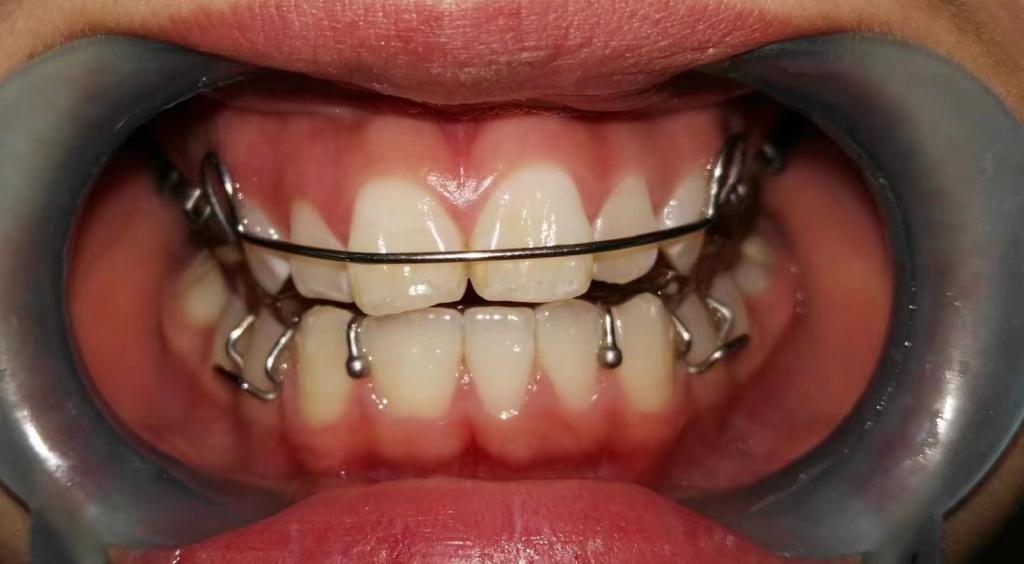

1. 前牙反合

前牙反合,俗称“地包天”,是指上下颌牙齿咬合时,下颌前牙咬在上颌前牙的外面。前牙反合随着患者的生长,症状会逐渐加重,往往造成上颌骨发育不足、下颌骨发育过度,表现为凹面型,对患者的美观、功能及心理健康均带来了极大的不良影响。乳牙列时期的前牙反合一般在3-5岁左右进行。混合牙列的前牙反合一般在8-9岁左右。

矫治方法:前牙反合的患儿往往伴有咬上唇、伸下巴、口呼吸等不良习惯。因此,应首先纠正其不良习惯。口呼吸习惯应进行耳鼻喉科会诊处理,检查其是否伴有鼻咽部疾病,排除鼻咽部疾病后,再进行纠正。对于乳牙列,常用的矫治器为合垫舌簧矫治器;对于混合牙列,常用的矫治器为前方牵引矫治器和FRⅢ矫治器。